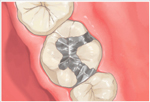

アメリカのヒューストン発のDoc's Best Cements(ドックベストセメントまたはドックスベストセメント)により痛くない、削らない、神経を取らない治療が可能になりました。(従来の保険治療で行うような予防的な拡大処置としてむし歯以外の健全な歯質を削らないということです。

まったく歯を削らないという意味ではありません。) ドックベストセメントは、Dr.Fraserが1990年に開発したミネラルを含んだ銅セメントです。

ドッグベストセメント治療は、銅、酸化亜鉛、酸化チタン、リン酸、水酸化アルミなどを主成分とする素材を使います。鉄(Fe)イオンと銅(Cu)イオンのコンビネーションによる殺菌力が、むし歯に効果的に作用することで、むし歯菌に侵された歯の象牙質の無菌化を促すという大きな働きがあります。

メリット一般的なむし歯治療と違い、ドッグベストセメント治療は必要以上に歯を削らないで済みますので、歯を削る違和感もなく、痛みを感じないので、麻酔注射も必要ない場合がほとんどです。

ドッグベストセメントの鉄(Fe)イオンと銅(Cu)イオンのコンビネーションによる殺菌力で患部を殺菌することで、神経を残せる可能性が高くなります。

むし歯菌に侵されている歯の内部の象牙質をドッグベストセメントの鉄(Fe)イオンと銅(Cu)イオンで殺菌することで、歯の象牙質部分の再石灰化を促します。